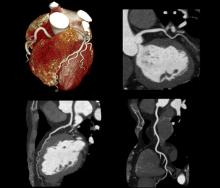

At RSNA23, Imaging Technology News (ITN) spoke with Bhvita Jani, principal analyst at Signify Research, about advancements and trends in medical imaging, including the development of coronary CTA, use of molecular imaging in theranostic applications, and remote acquisition support, as well as future outlooks and the evolution of medical imaging.